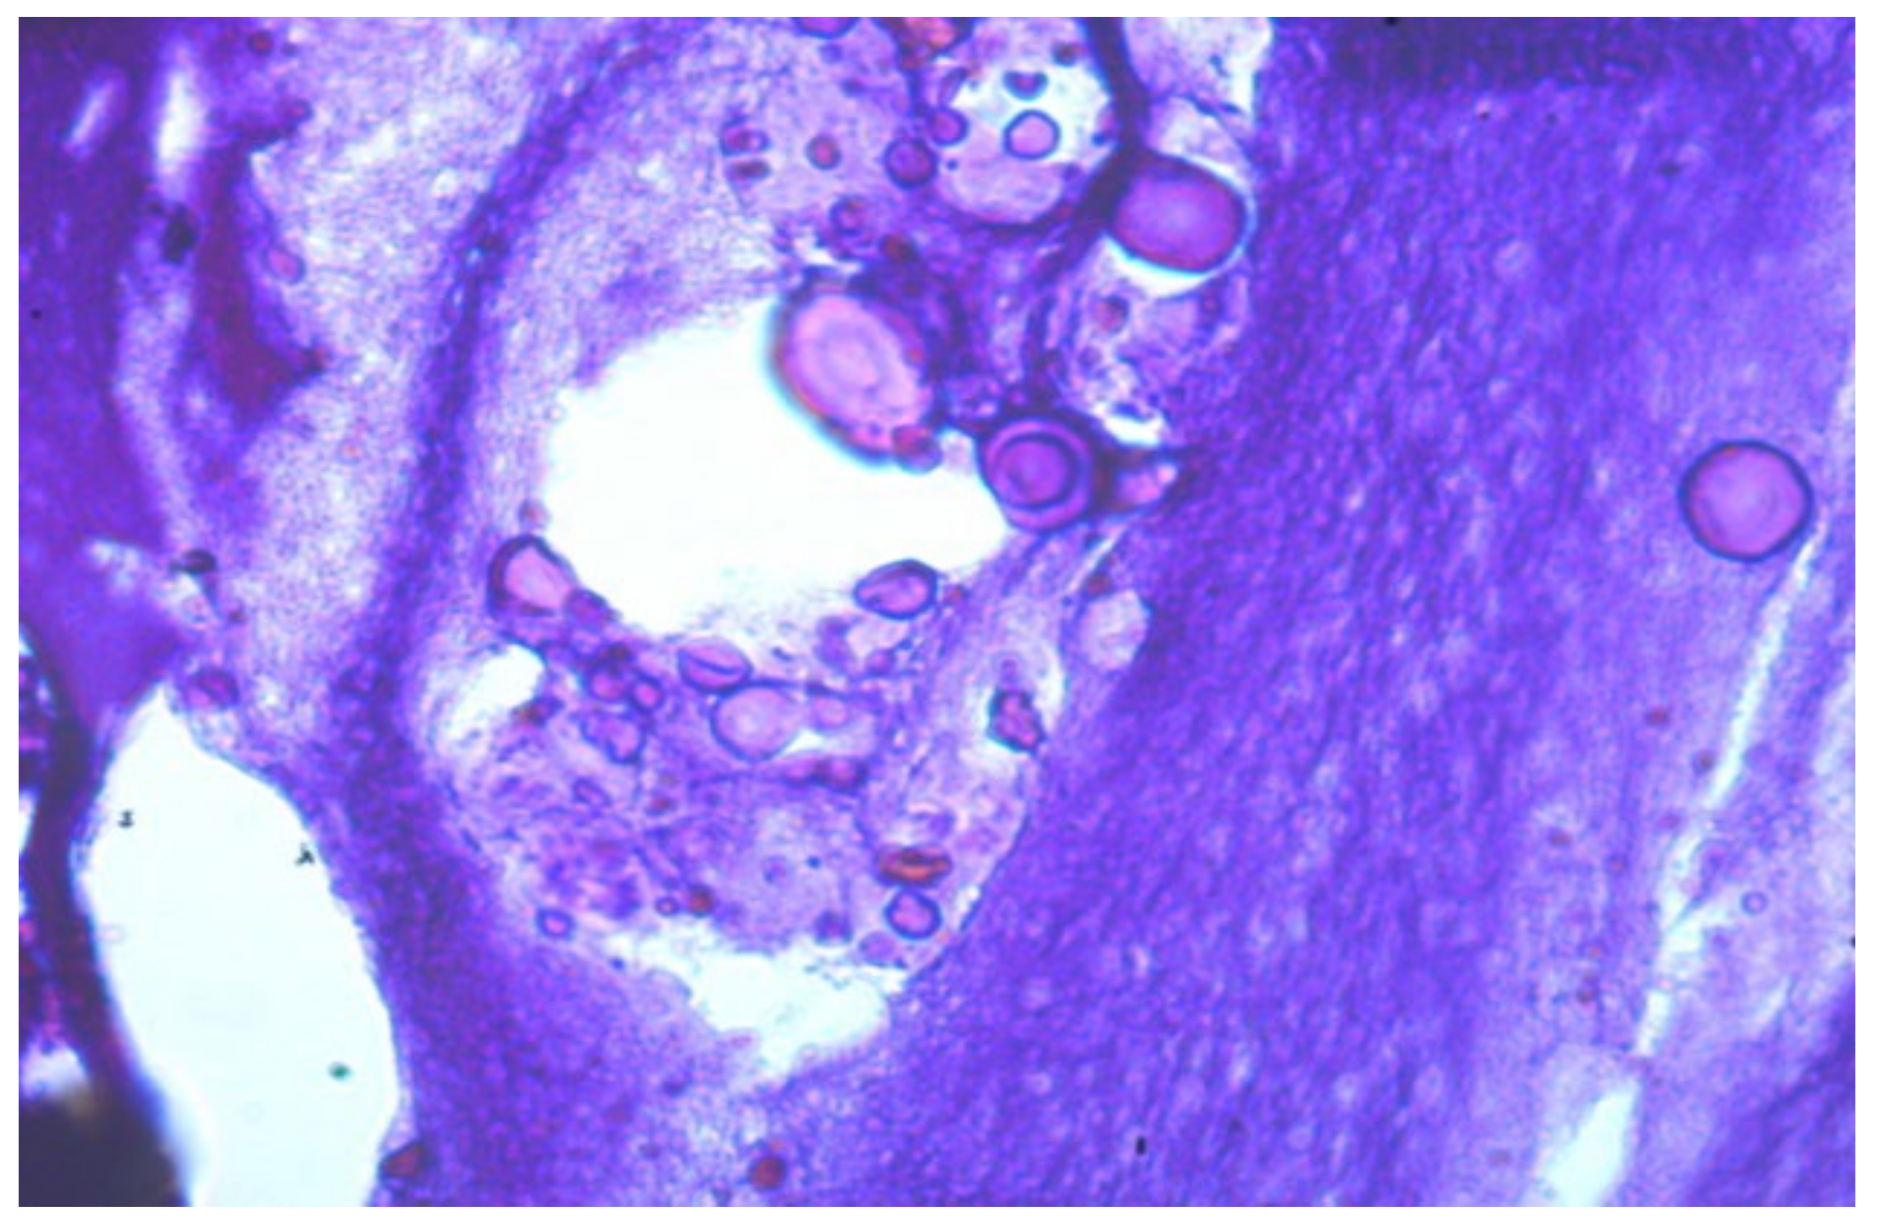

- Foreign substance (gel) migrated in the tissues, provoking the active growth of connective tissue;

- Aseptic and septic inflammatory reactions;

- Sections of round-shaped petrifications with clear contours;

- Lymphoid cell reaction, the presence of voids and necrotic masses, and the formation of cystic cavities;

- Pronounced deformation of adipocytes;

- Muscle tissue with extensive necrosis and effusion of the protein component;

- Numerous mast cells;

- Isolated, giant Pirogov–Langhans cells surrounded by lymphocytes and macrophages.